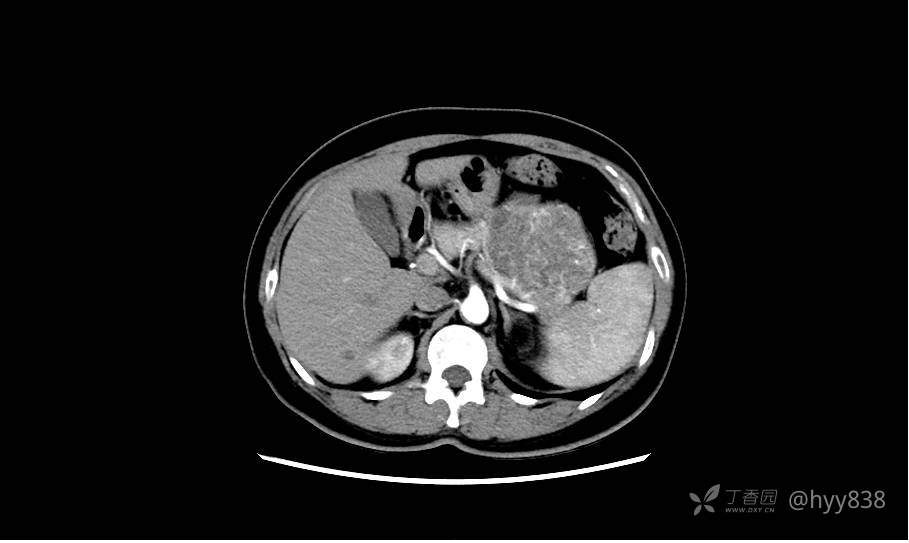

胰腺增强动脉期